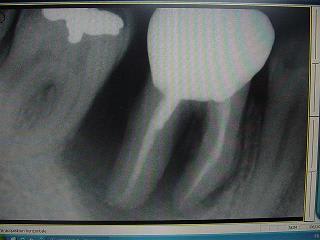

ci joint des retro de mars 2001 et aout 2003 de 46 qui montre l'evolution du cas..

bon, je suis loin d'etre d'acc avec vous consernant l'endo: regardez l'evolution de la lesion, de 2001 à 2003, sur les retro: il me semble très peu probable que l'endo ( pas top, ok mais d'apparence pas si tocarde) soit en cause. On voit en 2001 une atteinte distale, clairement paro.

En plus, problème endo sur 46, sur 35 et 17 qui engendrerais de telles lésion, c'est twilight zone! pour l'occlusion, je suis plus d'accord dans son role agravant important.